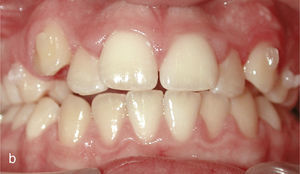

El paciente se presentó en nuestro centro con el siguiente cuadro: dentición permanente con proinclinación de dientes anteriores y desviación de la línea media, diente 53 persistente, dientes 13 y 23 elevados y desplazados hacia vestibular, curva de Spee marcada con extrusión del sector anteroinferior, dientes rotados y apiñados en maxilar y mandíbula, clase II de Angle con un resalte de 4mm y sobremordida de 0mm, además de ausencia de guía canina (figs. 13a a 13c y 14a a 14e).

El plan de tratamiento incluyó el establecimiento de una clase I de Angle con sobremordida horizontal y vertical fisiológicas mediante la distalización del sector posterosuperior, con corrección de los caninos superiores y aseguramiento de una guía canina. Las arcadas se dotaron además de una apariencia armoniosa eliminando la giroversión y los apiñamientos mediante la reducción del esmalte interproximal y el ajuste de las líneas medias. El paciente optó por un tratamiento con el sistema Invisalign alternativo a la aparatología fija con brackets. Se colocó un atache rectangular vertical en los dientes 13 y 23 y, en el curso del tratamiento, también en los dientes anterosuperiores y en el diente 43. Además durante todo el tratamiento el paciente llevó elásticos de clase II en ambos lados, del diente 14 al diente 46 y del diente 24 al diente 36 para obtener el anclaje necesario durante la distalización. La figura 15 muestra la situación intraoral de un caso similar con brackets en los dientes 13 y 46. En la zona de los brackets se acortó el alineador. Además de los alineadores se utilizaron elásticos de clase II del diente 13 al diente 46.